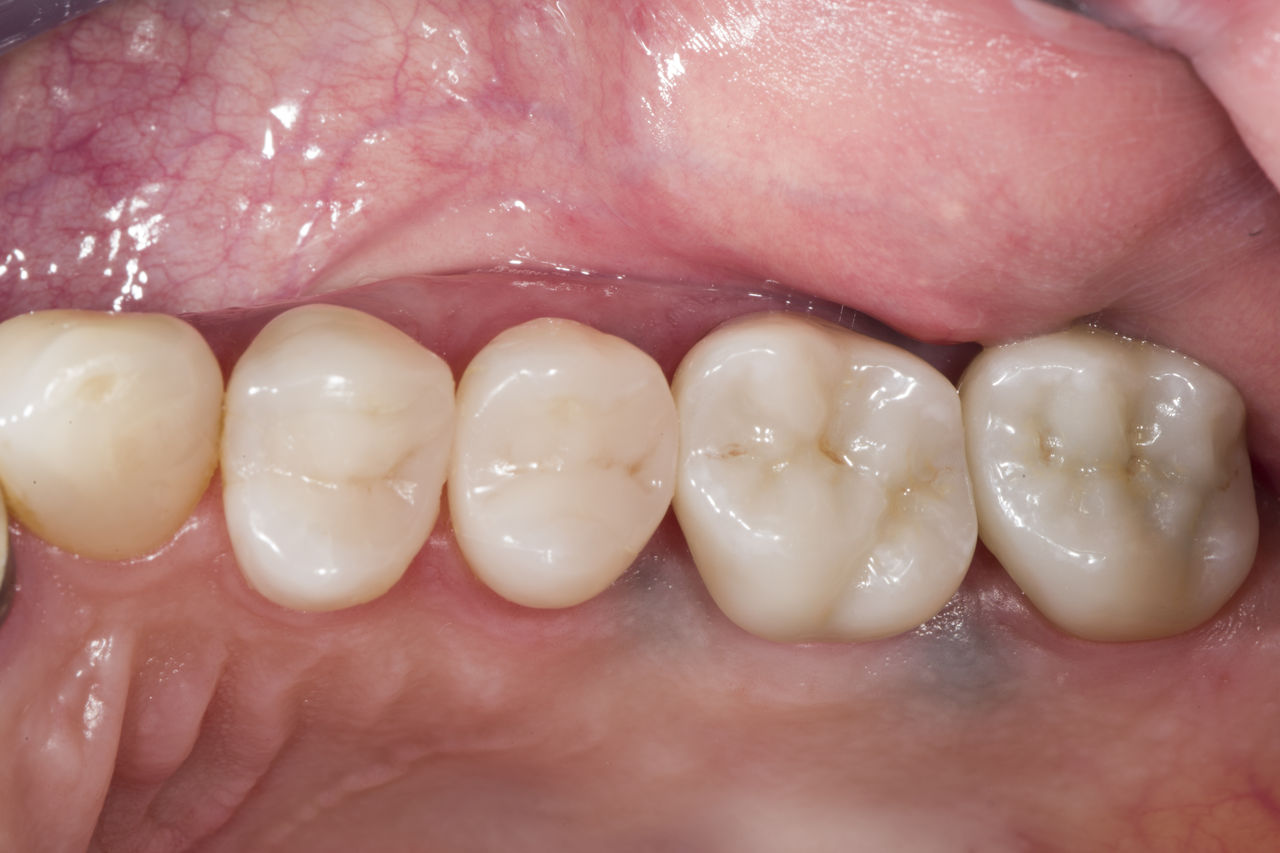

After

Chairside-fabricated restoration made from an advanced lithium-disilicate ceramic CEREC Tessera.